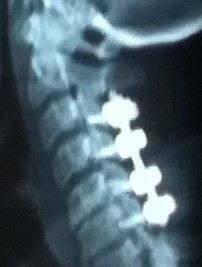

A case of a female patient in the fifth decade of life suffering from quadrilateral weakness and increased neurological reflexes due to her ossification or calcification of the dura mater against the third and fourth cervical vertebrae, and multiple cervical herniated discs as shown on CT and MRI scans.

A successful surgery was performed to expand the cervical nerve canal and stabilize the cervical vertebrae from the back, which resulted in decompression of the spinal cord in the cervical vertebrae, as shown by CT scans and MRI after surgery, and the patient recovered.